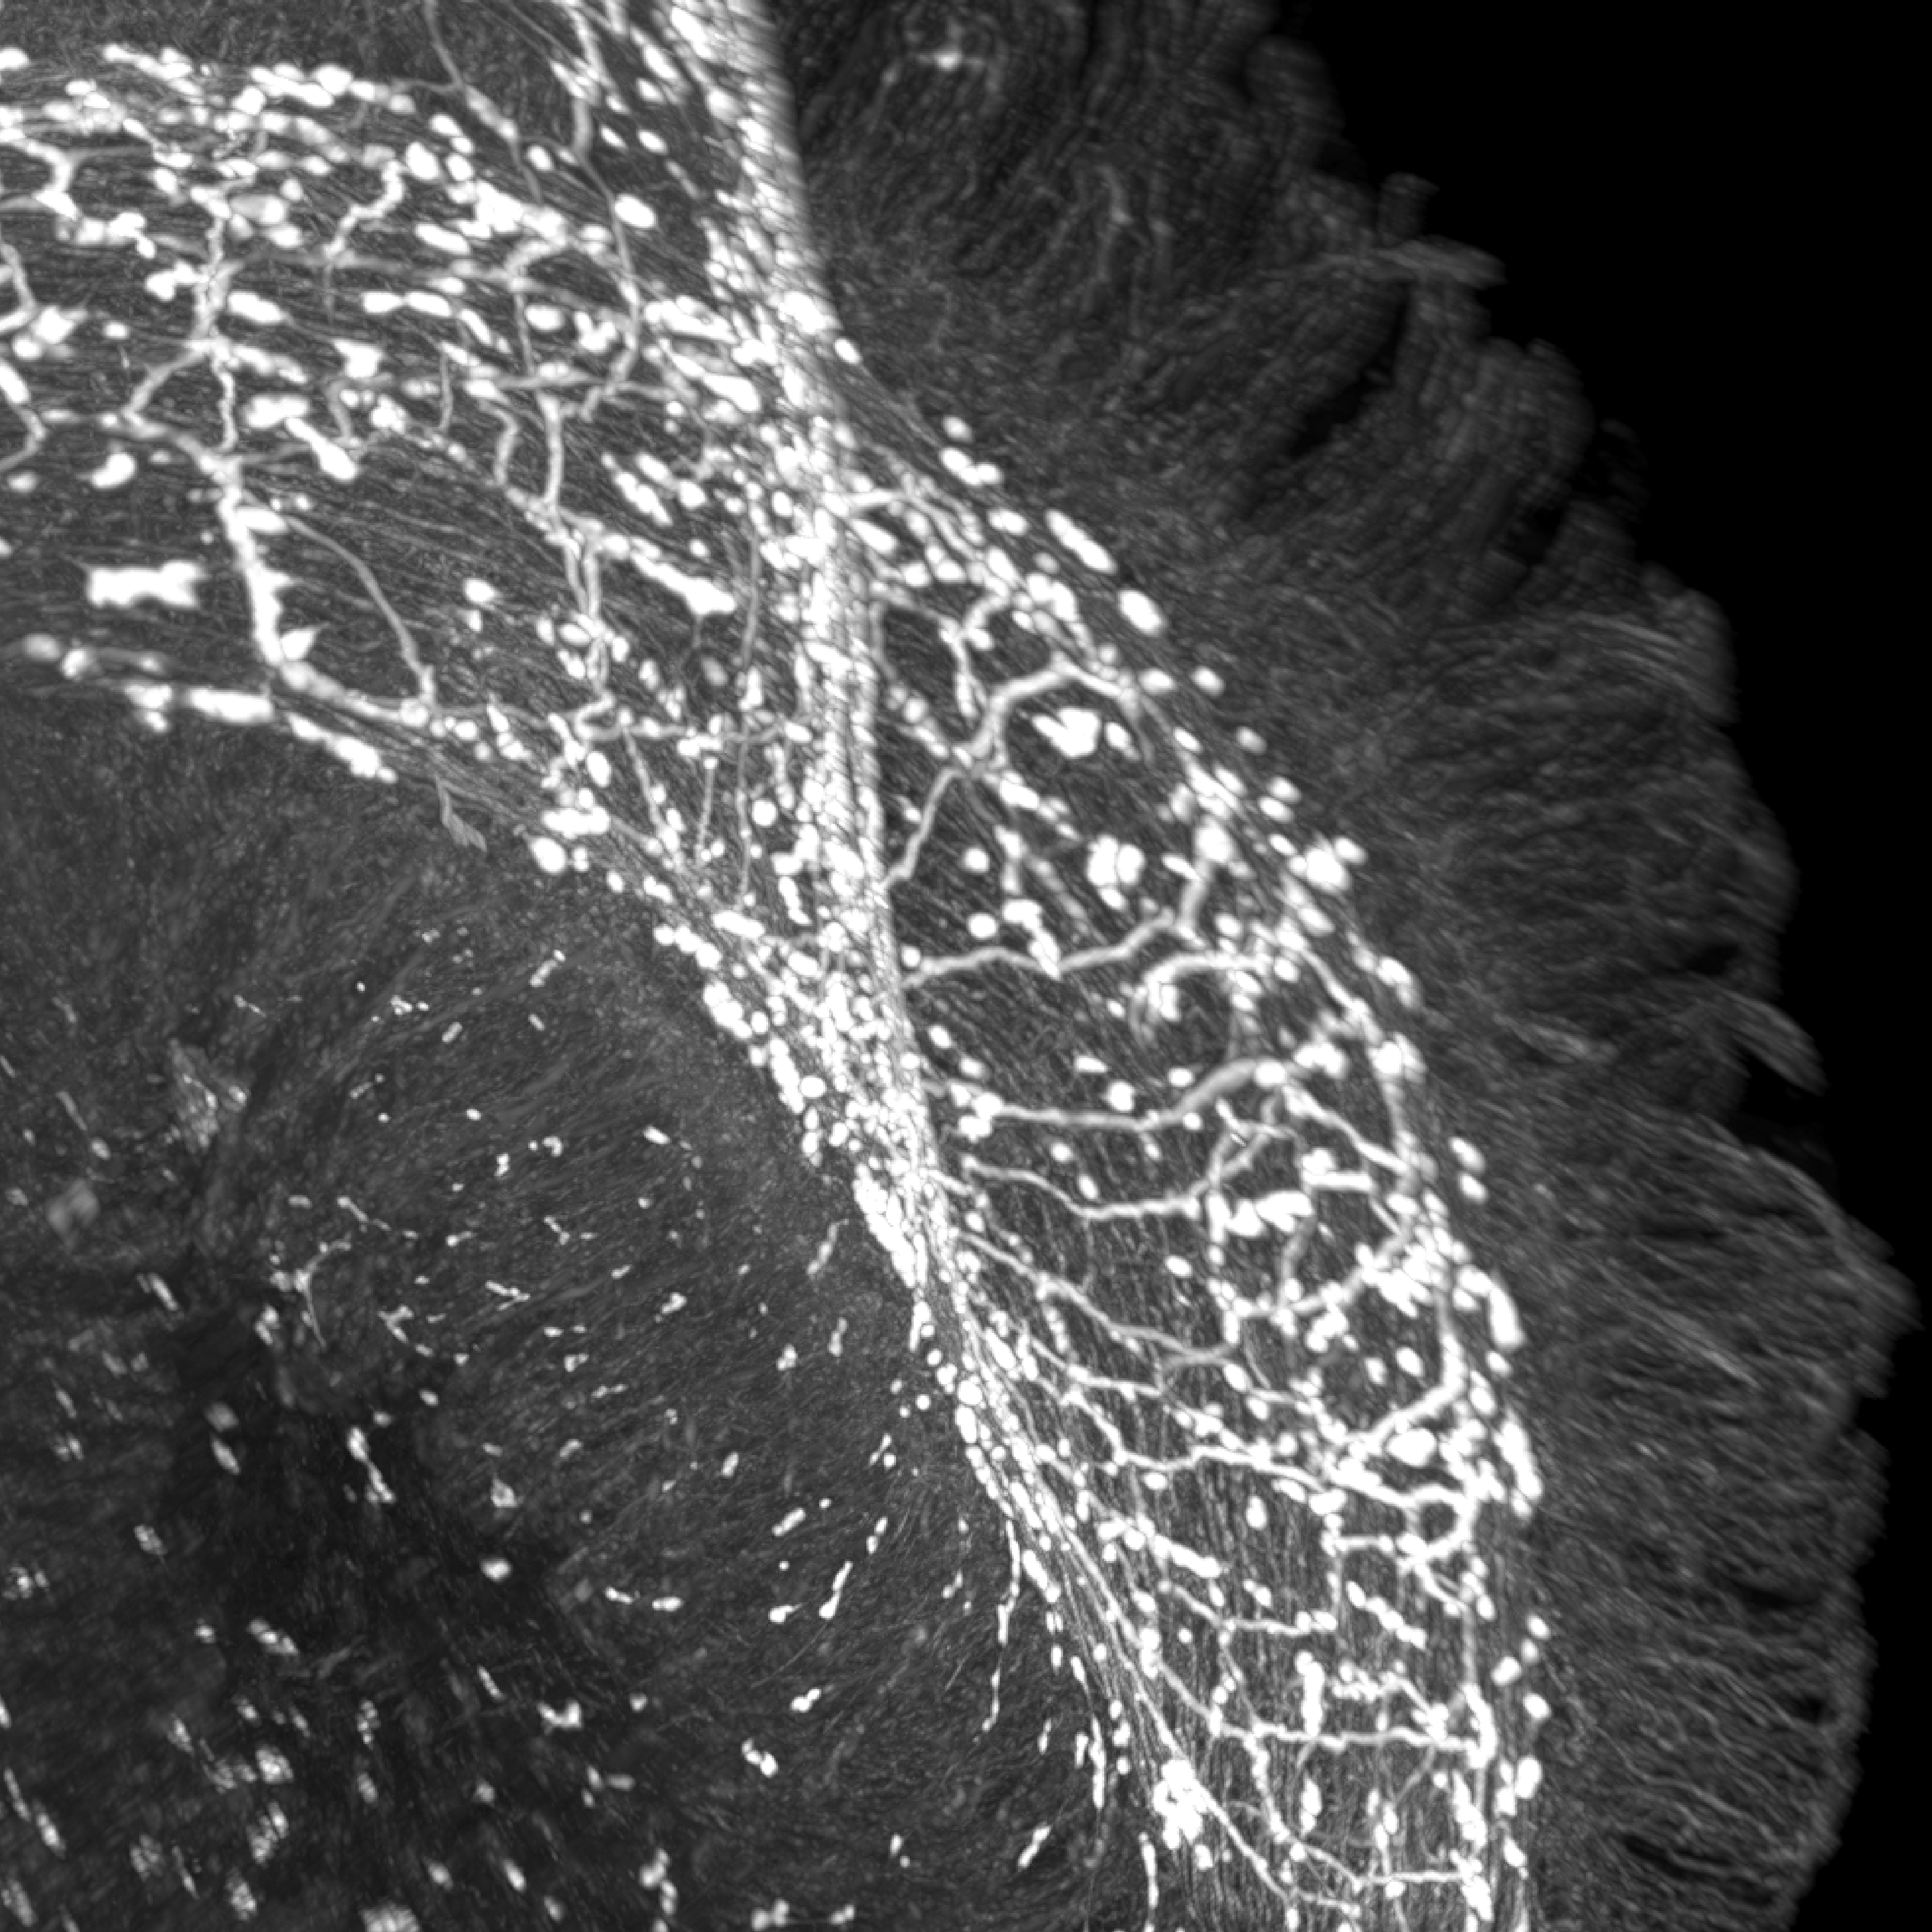

The researchers focused on a neurochemical messenger called VIP – short for vasoactive intestinal peptide – which is released by certain neurons in the gut. They found that neighbouring epithelial cells possess a receptor for VIP, called VIPR1, which acts like a receiver antenna. These epithelial cells form the front line between the body and the outside world, constantly exposed to food, microbes, and potential pathogens.

When the team experimentally activated VIP-releasing neurons in mice, the gut’s epithelial cells began producing cytokines that stimulate a type 1 immune response – the body’s “killer mode”, used to destroy bacteria and infected cells. But when they blocked the receptor VIPR1 in epithelial cells, the balance flipped: the killer response weakened, while a type 2 immune response – the one that drives repair and fights parasites – grew stronger.

The shift was striking. Mice lacking VIPR1 in their epithelial cells became more vulnerable to bacterial infections like Salmonella, yet more resistant to parasitic worms. “This was the big surprise”, says Roksana Pirzgalska, first author of the study. “We realised the neurons of the gut are not just fine-tuning immunity locally – they are orchestrating completely different immune programmes”.

In other words, the gut’s nervous system sits at the railway switch, sensing the environment and deciding which track the immune system should take. When the “killer” track is active, immune cells patrol the intestinal lining, eliminating bacteria and tumour cells. When the “repair” track is engaged, the same tissue focuses on regeneration – rebuilding the delicate epithelial barrier that keeps harmful microbes out.

But how do epithelial cells pass on the message once they’ve received the VIP signal? “We found that these cells translate the nerve signal into a set of molecular instructions – a cocktail of ‘cytokines’, the chemical messengers of the immune system”, explains Pirzgalska. “You can think of cytokines as the language that epithelial cells use to talk to immune cells. Different immune cells have different receptors for these cytokines, so depending on which ones are released, the immune system knows whether to attack or repair”.